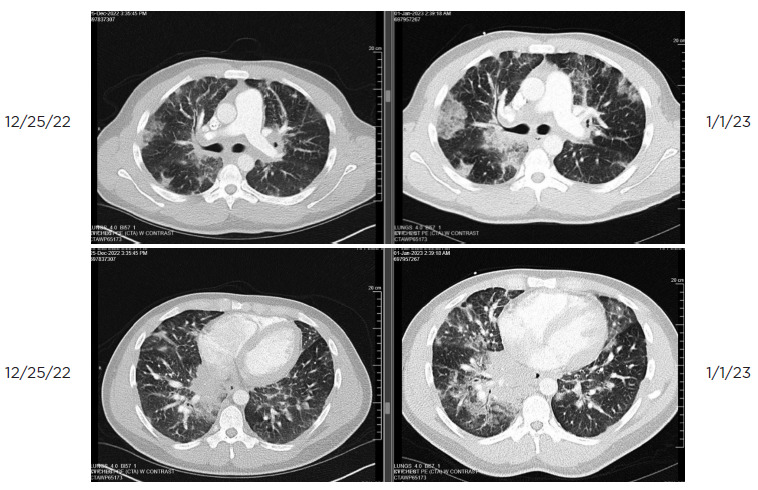

Medullary renal cell carcinomas are exceedingly rare and essentially uniformly and rapidly fatal. Expeditious diagnosis is crucial. Immediate treatment with a clinical trial or platinum-based chemotherapy is needed for metastatic disease given the aggressive nature of medullary renal cell carcinomas. In this article, we discuss a 24-year-old man with no known significant past medical history who presented with a progressive cough and shortness of breath. After evaluation at an urgent care and four evaluations in the emergency department, the patient was admitted and ultimately diagnosed with metastatic medullary renal cell carcinoma. This case highlights the characteristics, presentation, rarity, and aggressiveness of medullary renal cell carcinoma.